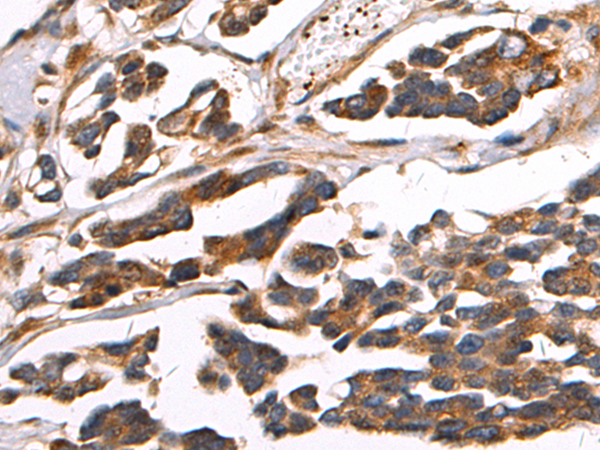

IHC 1/50-1/100 Human,Mouse,Rat

PIWIL2 antibodies are widely used in molecular biology and clinical research to investigate protein expression patterns, subcellular localization, and functional mechanisms. They enable techniques like Western blotting, immunohistochemistry, and immunofluorescence, helping researchers map PIWIL2's tissue-specific distribution, particularly in reproductive tissues, embryonic stem cells, and certain cancers. Aberrant PIWIL2 expression has been implicated in tumorigenesis, with studies linking its overexpression to testicular, breast, and gastrointestinal cancers, suggesting potential roles as a diagnostic biomarker or therapeutic target.